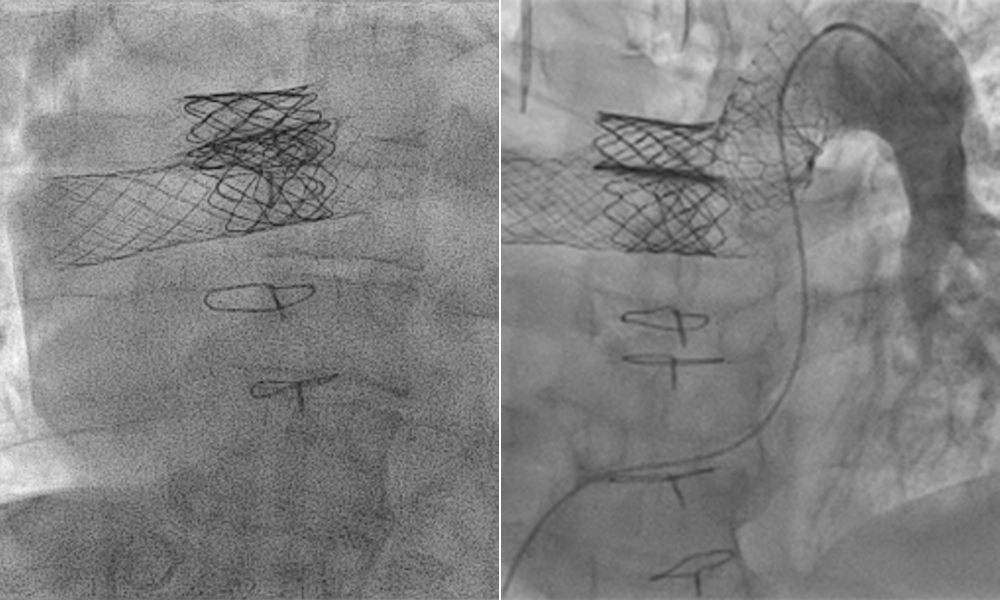

To reduce the right pulmonary artery diameter, a novel technique was devised by the pediatric cardiac catheterization team. Side-by-side transcatheter valves were placed in the right pulmonary artery in a superior-inferior orientation. This was the first time this technique had been described in the literature.

• Two Cook XL 4010 stents were placed in superior-inferior orientation simultaneously (deployed at 18 millimeters and 20 millimeters respectively).

• Inferior stent migrated distally; superior stent kept secure by leaving balloon inflated.

• Wire position was lost across inferior stent but obtained via internal jugular approach.

• A Cook XL 5010 was placed interlocking with the first inferior stent followed by a 22 millimeter Melody Valve on 20 mm Ensemble in inferior stent and 22 mm Melody Valve on 18 millimeter Ensemble in superior stent.

• Five weeks later, a Cook XL 5010 stent was deployed into the left pulmonary artery followed by a 26 millimeter Sapien S3.

Both Melody valves are in stable position within the right pulmonary artery (left); after second catheterization, the Sapien S3 is in appropriate location within the left pulmonary artery (right).